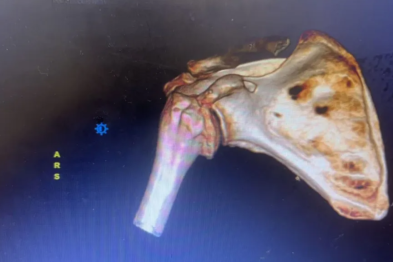

术后并发假性动脉瘤?燕达医院血管外科微创封堵术给出规范化解决方案